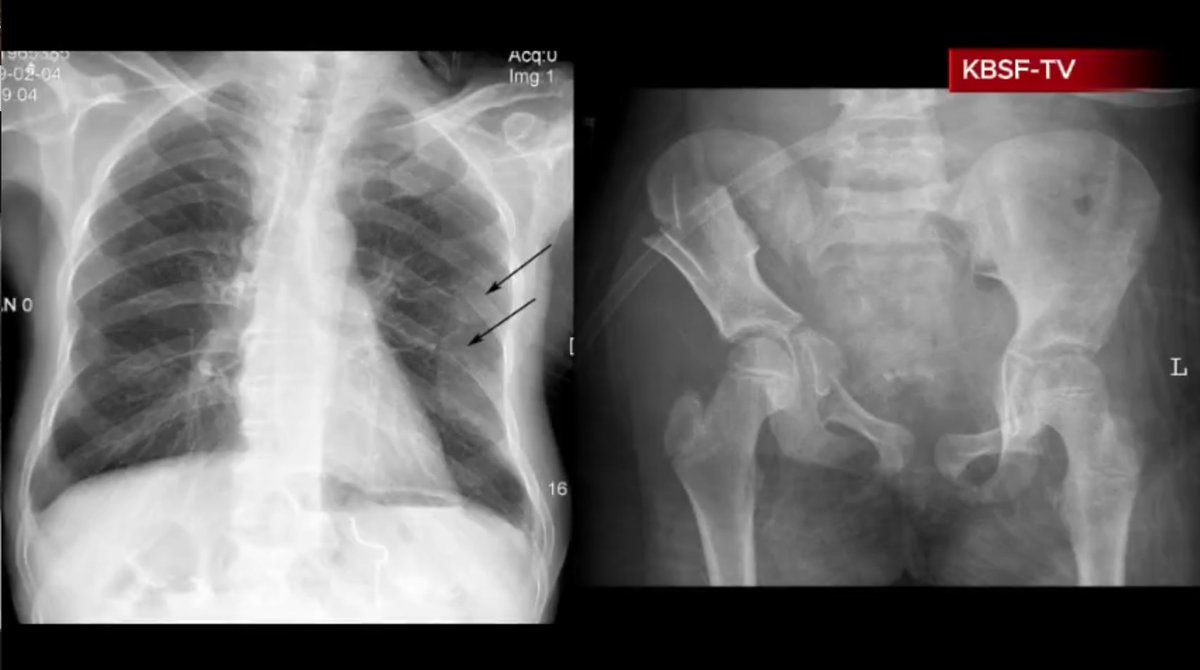

And finally, the video shows us these two X-rays as evidence that Alicia Brown has become paralyzed.

Both of these supposed Alicia Brown X-rays have been lifted from medical research journals on the internet and can be found via reverse image search. Here they are:

https://www.researchgate.net/figure/X-ray-image-A-chest-radiograph-showed-fractures-of-the-left-sixth-and-seventh-ribs_fig4_47458589